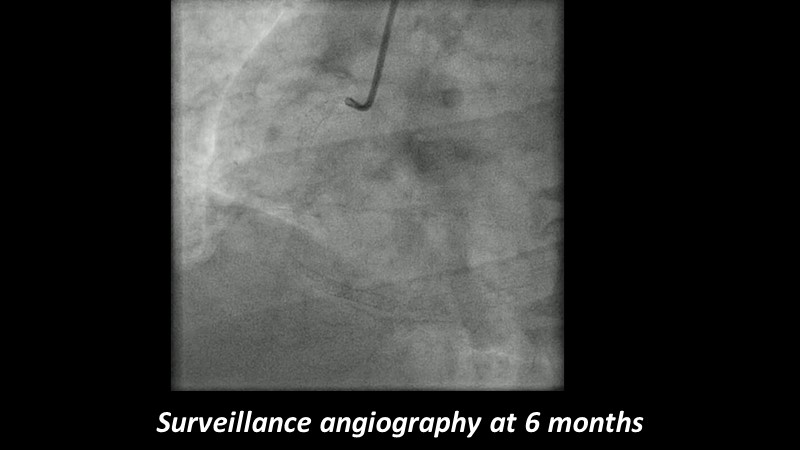

Go implant-free in de novo lesions: DCB-only strategy

Consult this session to learn about the DCB-only concept, treatment methodology and consensus group recommendations, and discover the latest scientific evidence of DCB-only in de novo lesions and in complex PCIs.